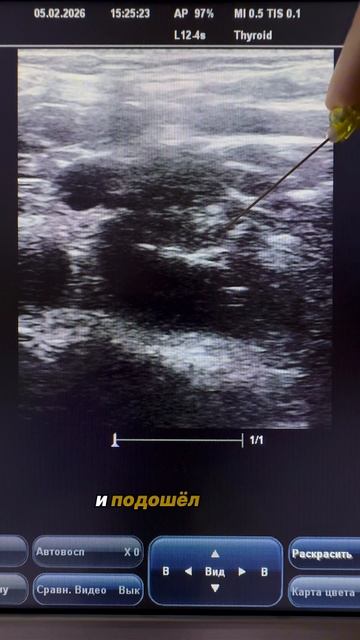

Торакоабдоминальное ранение с повреждением левого легкого, сердца и печени

История такая. Был в операционной. Позвали сделать e-FAST. Осколок в печени....